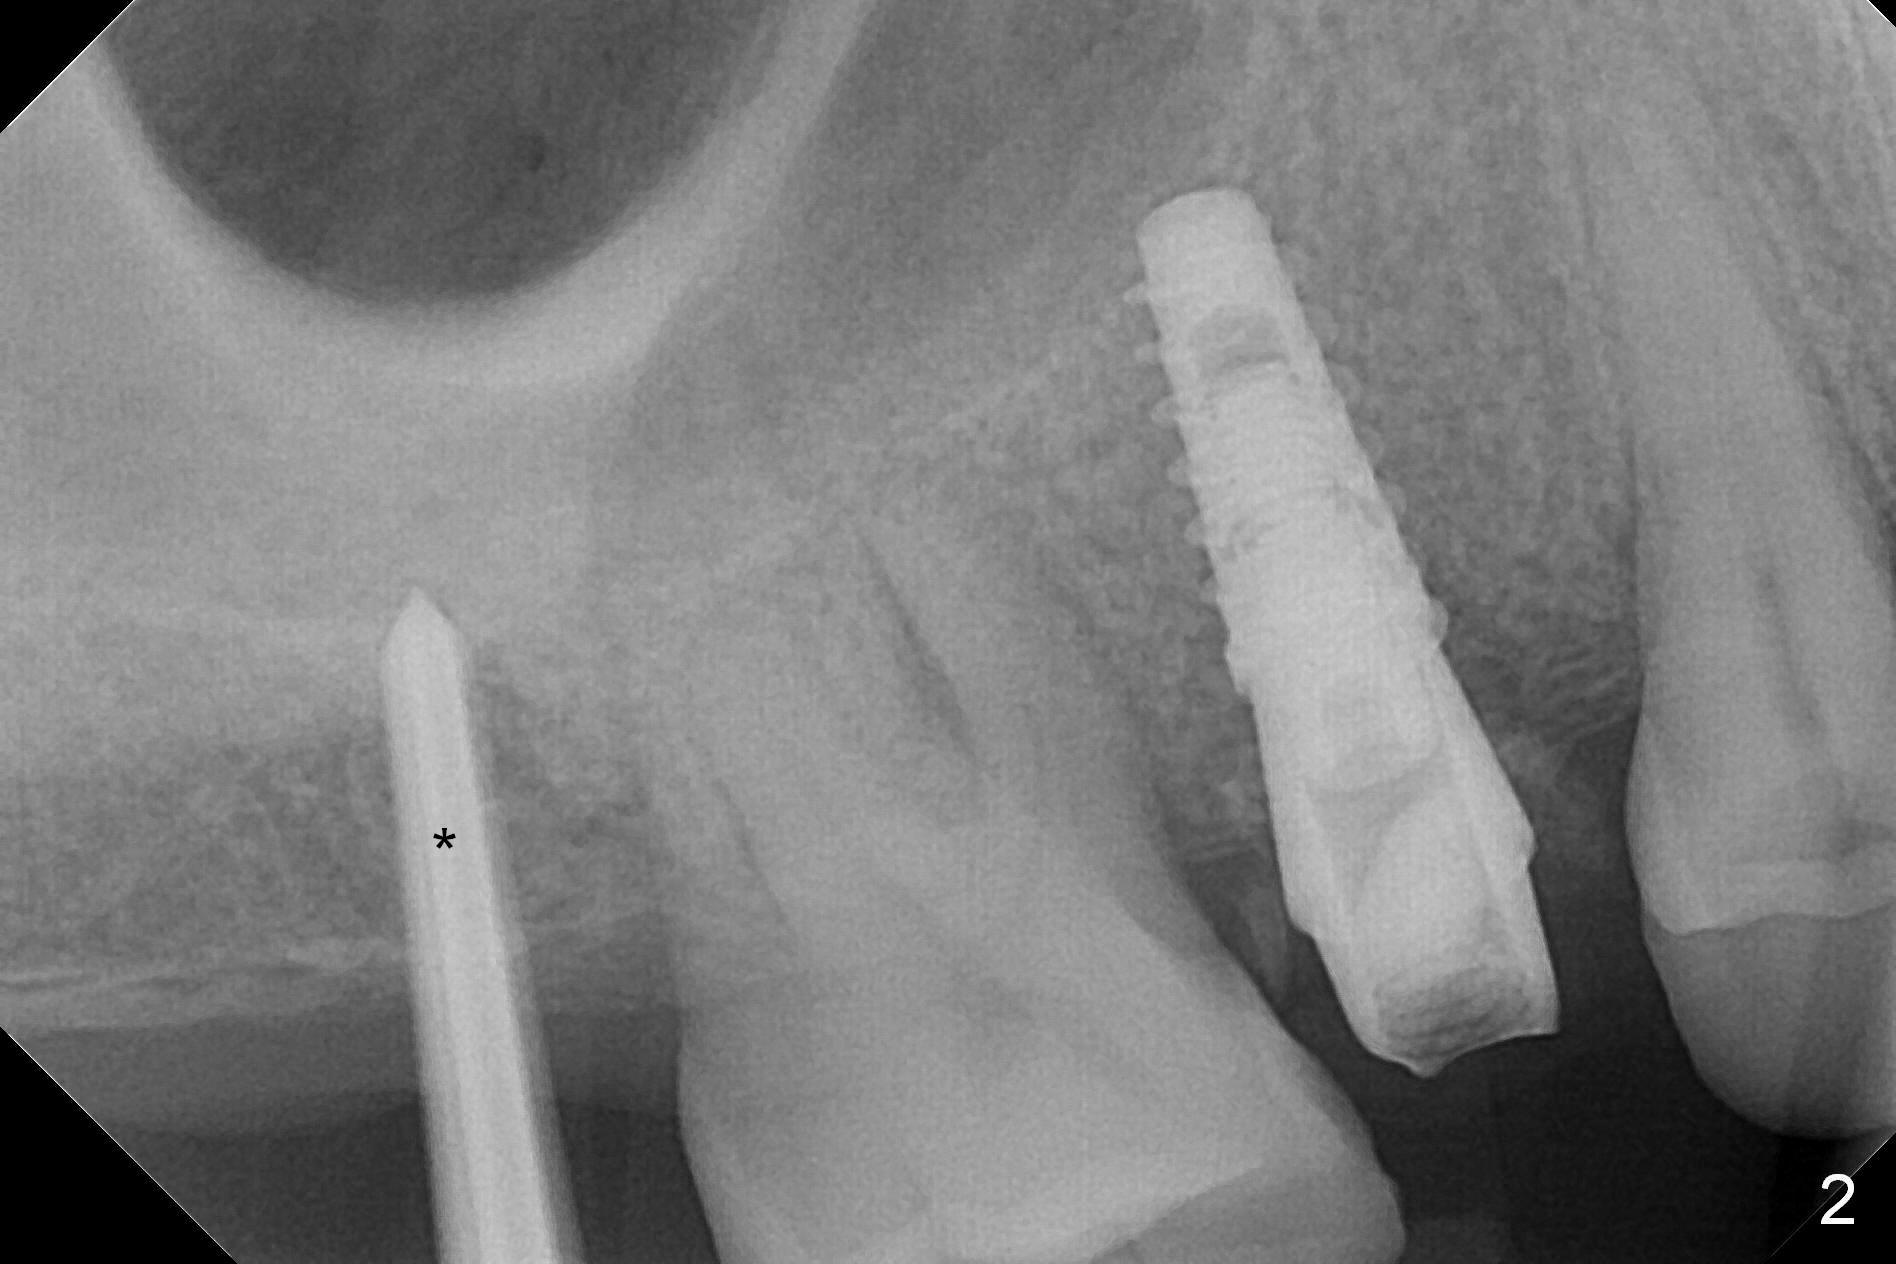

Since the ridge at the site of #2 is wide (Fig.1), Magic Split is used for access and bone density determination. In fact it enters for 9 mm (gingival level), followed by Magic Expander (ME) 3 mm (Fig.2 *). The center of the latter is 3.9 mm from the distal surface of the tooth #3. Lindamann bur is used to move the osteotomy distal, followed by sequential use of MEs until 4.3 mm one. When a 5x9 mm dummy implant is placed, its center is somewhat mesial (Fig.3 brown line). What needs to be done is change the trajectory to the red line so that the coronal end of the definitive implant (5.5x9 mm) will be placed evenly subcrestal (Fig.4,5). It is what happens, although slightly too subcrestal. Insertion torque is <35 Ncm; a 6x4 mm healing abutment is placed. ME 4.8 mm has to be tapped for 13 mm from gingival margin in order to let the implant penetrate the sinus floor. IBS implants seem to lack self tapping ability. Its tap drills should possess this capacity. Allograft/autogenous bone (harvested from dummy implant) is placed prior to implantation. The patient returns for impression 6 months postop (Fig.6,7; #4). A 5x4(3) mm abutment is placed; its height is reduced as well as the opposing supraerupted tooth (Fig.5) prior to impression.